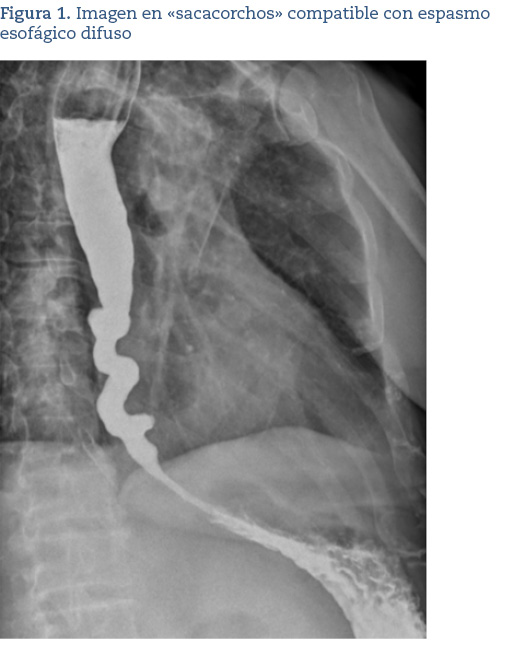

Se hizo una analítica completa consistente en un hemograma, glucemia, perfil renal, perfil hepático, perfil tiroideo y reactantes de fase aguda, siendo, en su conjunto, rigurosamente normal. La radiografía de tórax fue compatible con la normalidad, salvo signos artrósicos en columna dorsal. Posteriormente, se solicitó desde nuestra consulta un estudio esofagogastroduodenal (figura 1) para descartar posible causa mecánica o disfunción motora, en el que se evidenció un esófago con morfología en sacacorchos, sin claros signos de acalasia, sugestivo de espasmo esofágico difuso. Ante este último hallazgo y lo sintomático que estaba el paciente, se decidió su derivación a la consulta de digestivo. En dicha consulta, se confirmó el diagnóstico mediante manometría esofágica de alta resolución, donde se objetivó una peristalsis fallida en el tercio proximal con las degluciones líquidas.

La radiografía baritada puede jugar un importante papel para el diagnóstico de esta patología en nuestra consulta de Atención Primaria, dada la fácil accesibilidad y la casi inocuidad de la misma. Esta prueba puede mostrar una contractilidad desordenada o la clásica pero inhabitual imagen de «esófago en sacacorchos»4,5, como así fue en nuestro caso.